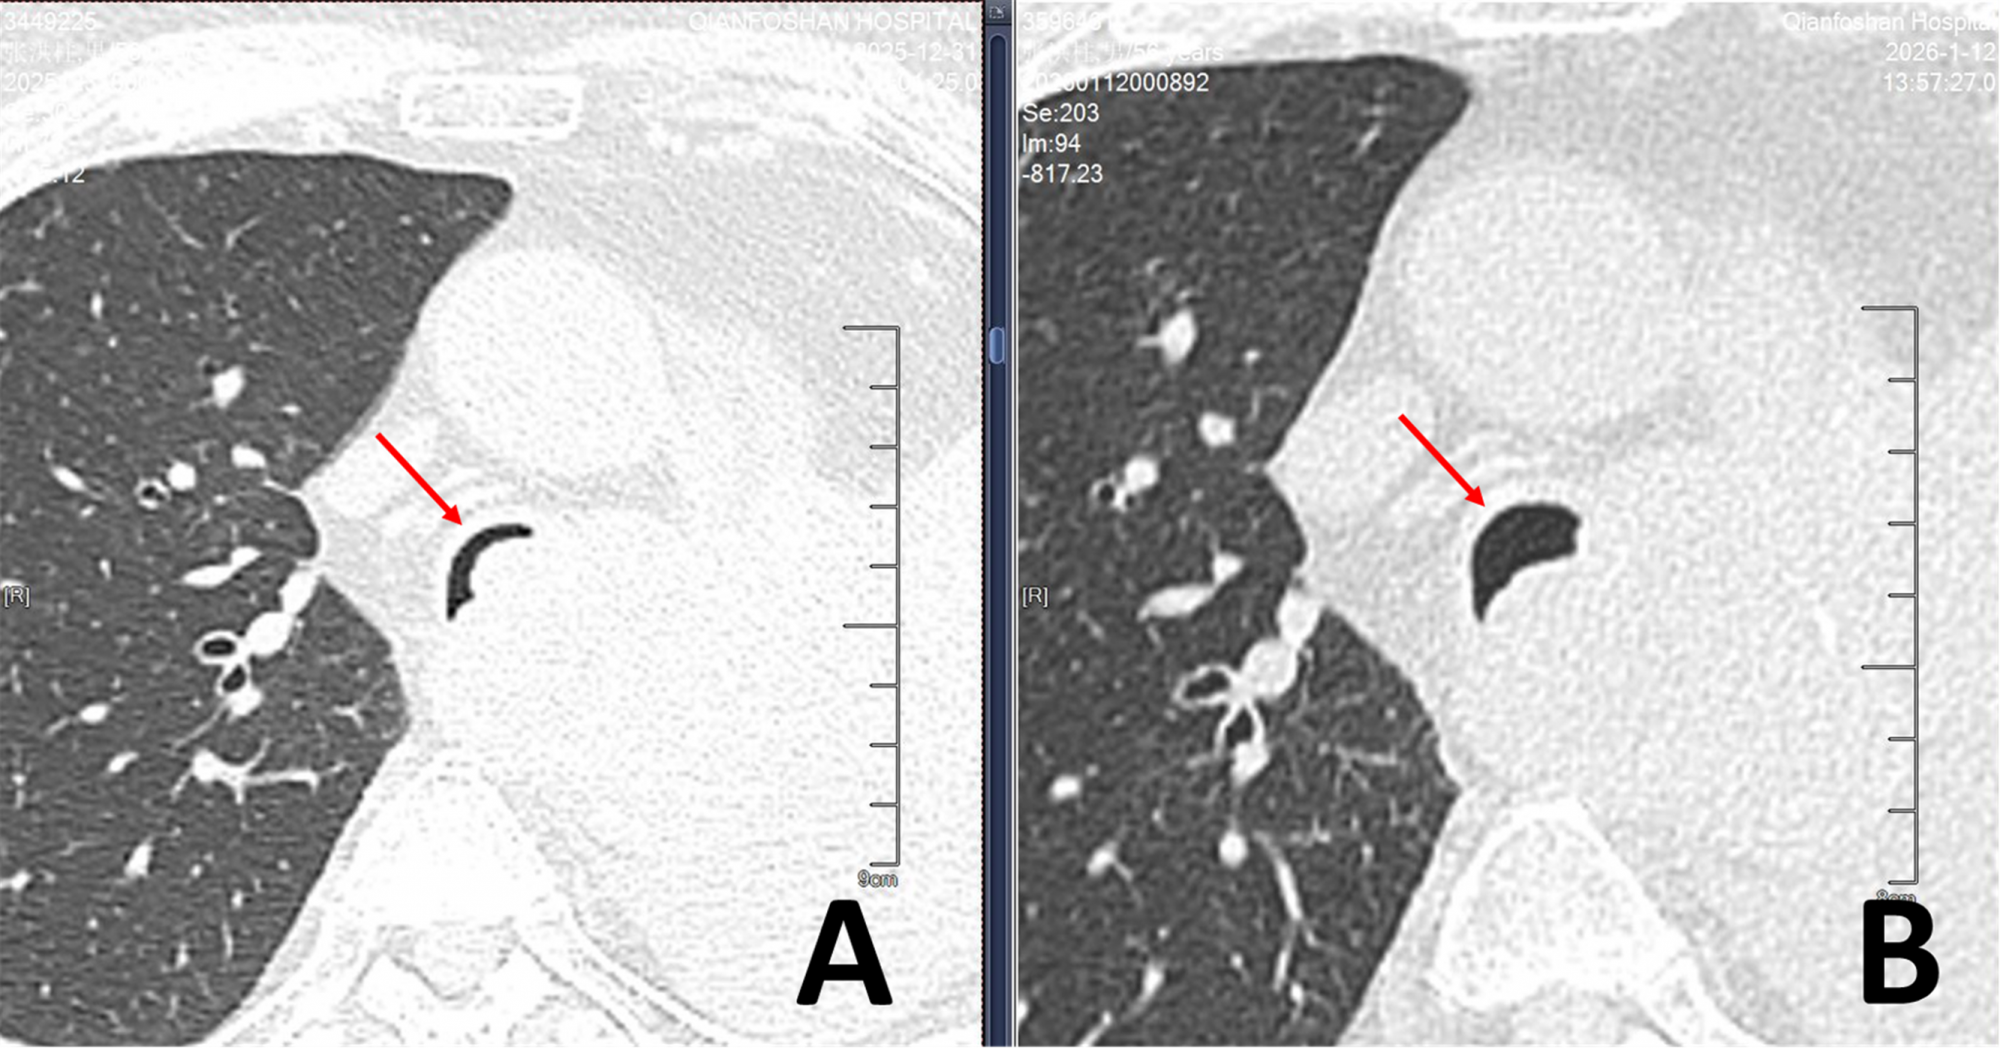

“鲁主任,我父亲...咳...又喘不上气了...”,张先生的儿子拿着最新的CT片,手指微微颤抖,快步跑进医院呼吸与危重症医学科副主任鲁德玕的办公室。患者胸部CT上清晰显示:主气管内新生物几乎填满了管腔,只留下一条月牙一样的极窄的缝隙,最宽处也不足2毫米(图片1:A)。

▲图1:气管镜介入治疗前后胸部CT对比

(A:治疗前,气管重度狭窄;B:治疗后,气管通畅)

血氧饱和度87%,呼吸频率38次/分,三凹征明显。胸部CT显示气管阻塞超过90%,正常成人的主气管平均直径约1.5-2.0厘米,90%的气道堵塞意味着气道堵塞状态下残留有效通气横截面积——还不及一根吸管的横截面积。